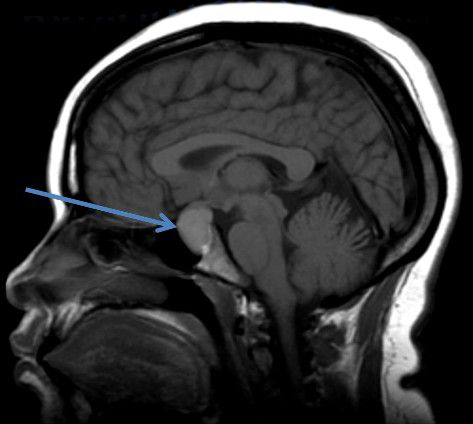

Киста кармана Ратке (Rathke's cleft cyst) — это доброкачественное образование в проекции седловидного углубления в основании черепа, известного как турецкое седло.

Киста кармана Ратке [24]

- Магнитно-резонансная томография (МРТ). Это основной способ диагностики кист кармана Ратке. МРТ позволяет получить изображения структур головного мозга в высоком разрешении и хорошо рассмотреть кисту, определить её размеры, форму, наличие содержимого и влияние на окружающие ткани. Этот метод наиболее информативен, а также безопасен, так как при получении изображений не используется рентгеновское излучение [18]. Кисты кармана Ратке располагаются обычно по средней линии, их полость однокамерная, без перемычек, с однородным МР-сигналом. В 65–75 % при МРТ внутри кист обнаруживаются узелки с характерными сигналами [23].